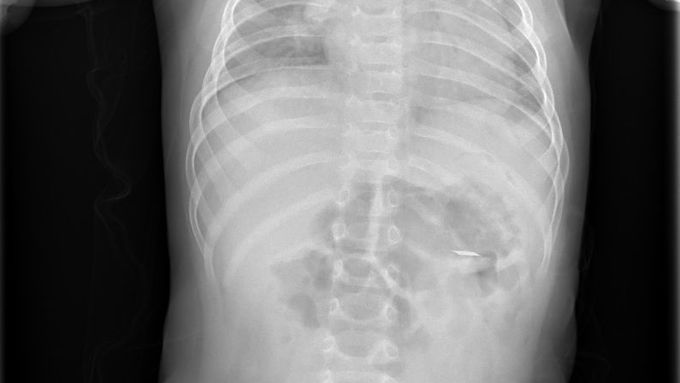

Zatímco dospělí vnímají produkty pro užívání zahřívaného tabáku jako moderní alternativu ke klasickému kouření, pro děti mohou představovat závažné zdravotní riziko. Pediatrická klinika 2. LF UK a FN Motol v uplynulém roce hospitalizovala deset dětí ve věku od osmi do patnácti měsíců, které pozřely ostrý kovový plíšek pocházející z těchto produktů.

"U tří malých pacientů jsme museli provést urgentní endoskopický zákrok, ve zbylých případech byly děti sledovány při hospitalizaci až do samovolného odchodu cizího tělesa. Kovový plíšek má ostré hrany a může poškodit trávicí trakt, v krajním případě by mohlo dojít i k perforaci," upozorňuje lékařka Kristýna Zárubová z Oddělení dětské gastroenterologie Pediatrické kliniky 2. LF UK a FN Motol.

Součástí některých náplní nebo ohřívacích jednotek však mohou být drobné kovové prvky - zejména tenké kovové plíšky, které se při neopatrné manipulaci mohou uvolnit. Pokud se následně dostanou do rukou malých dětí, které často vkládají předměty do úst, vzniká vážné riziko poranění.